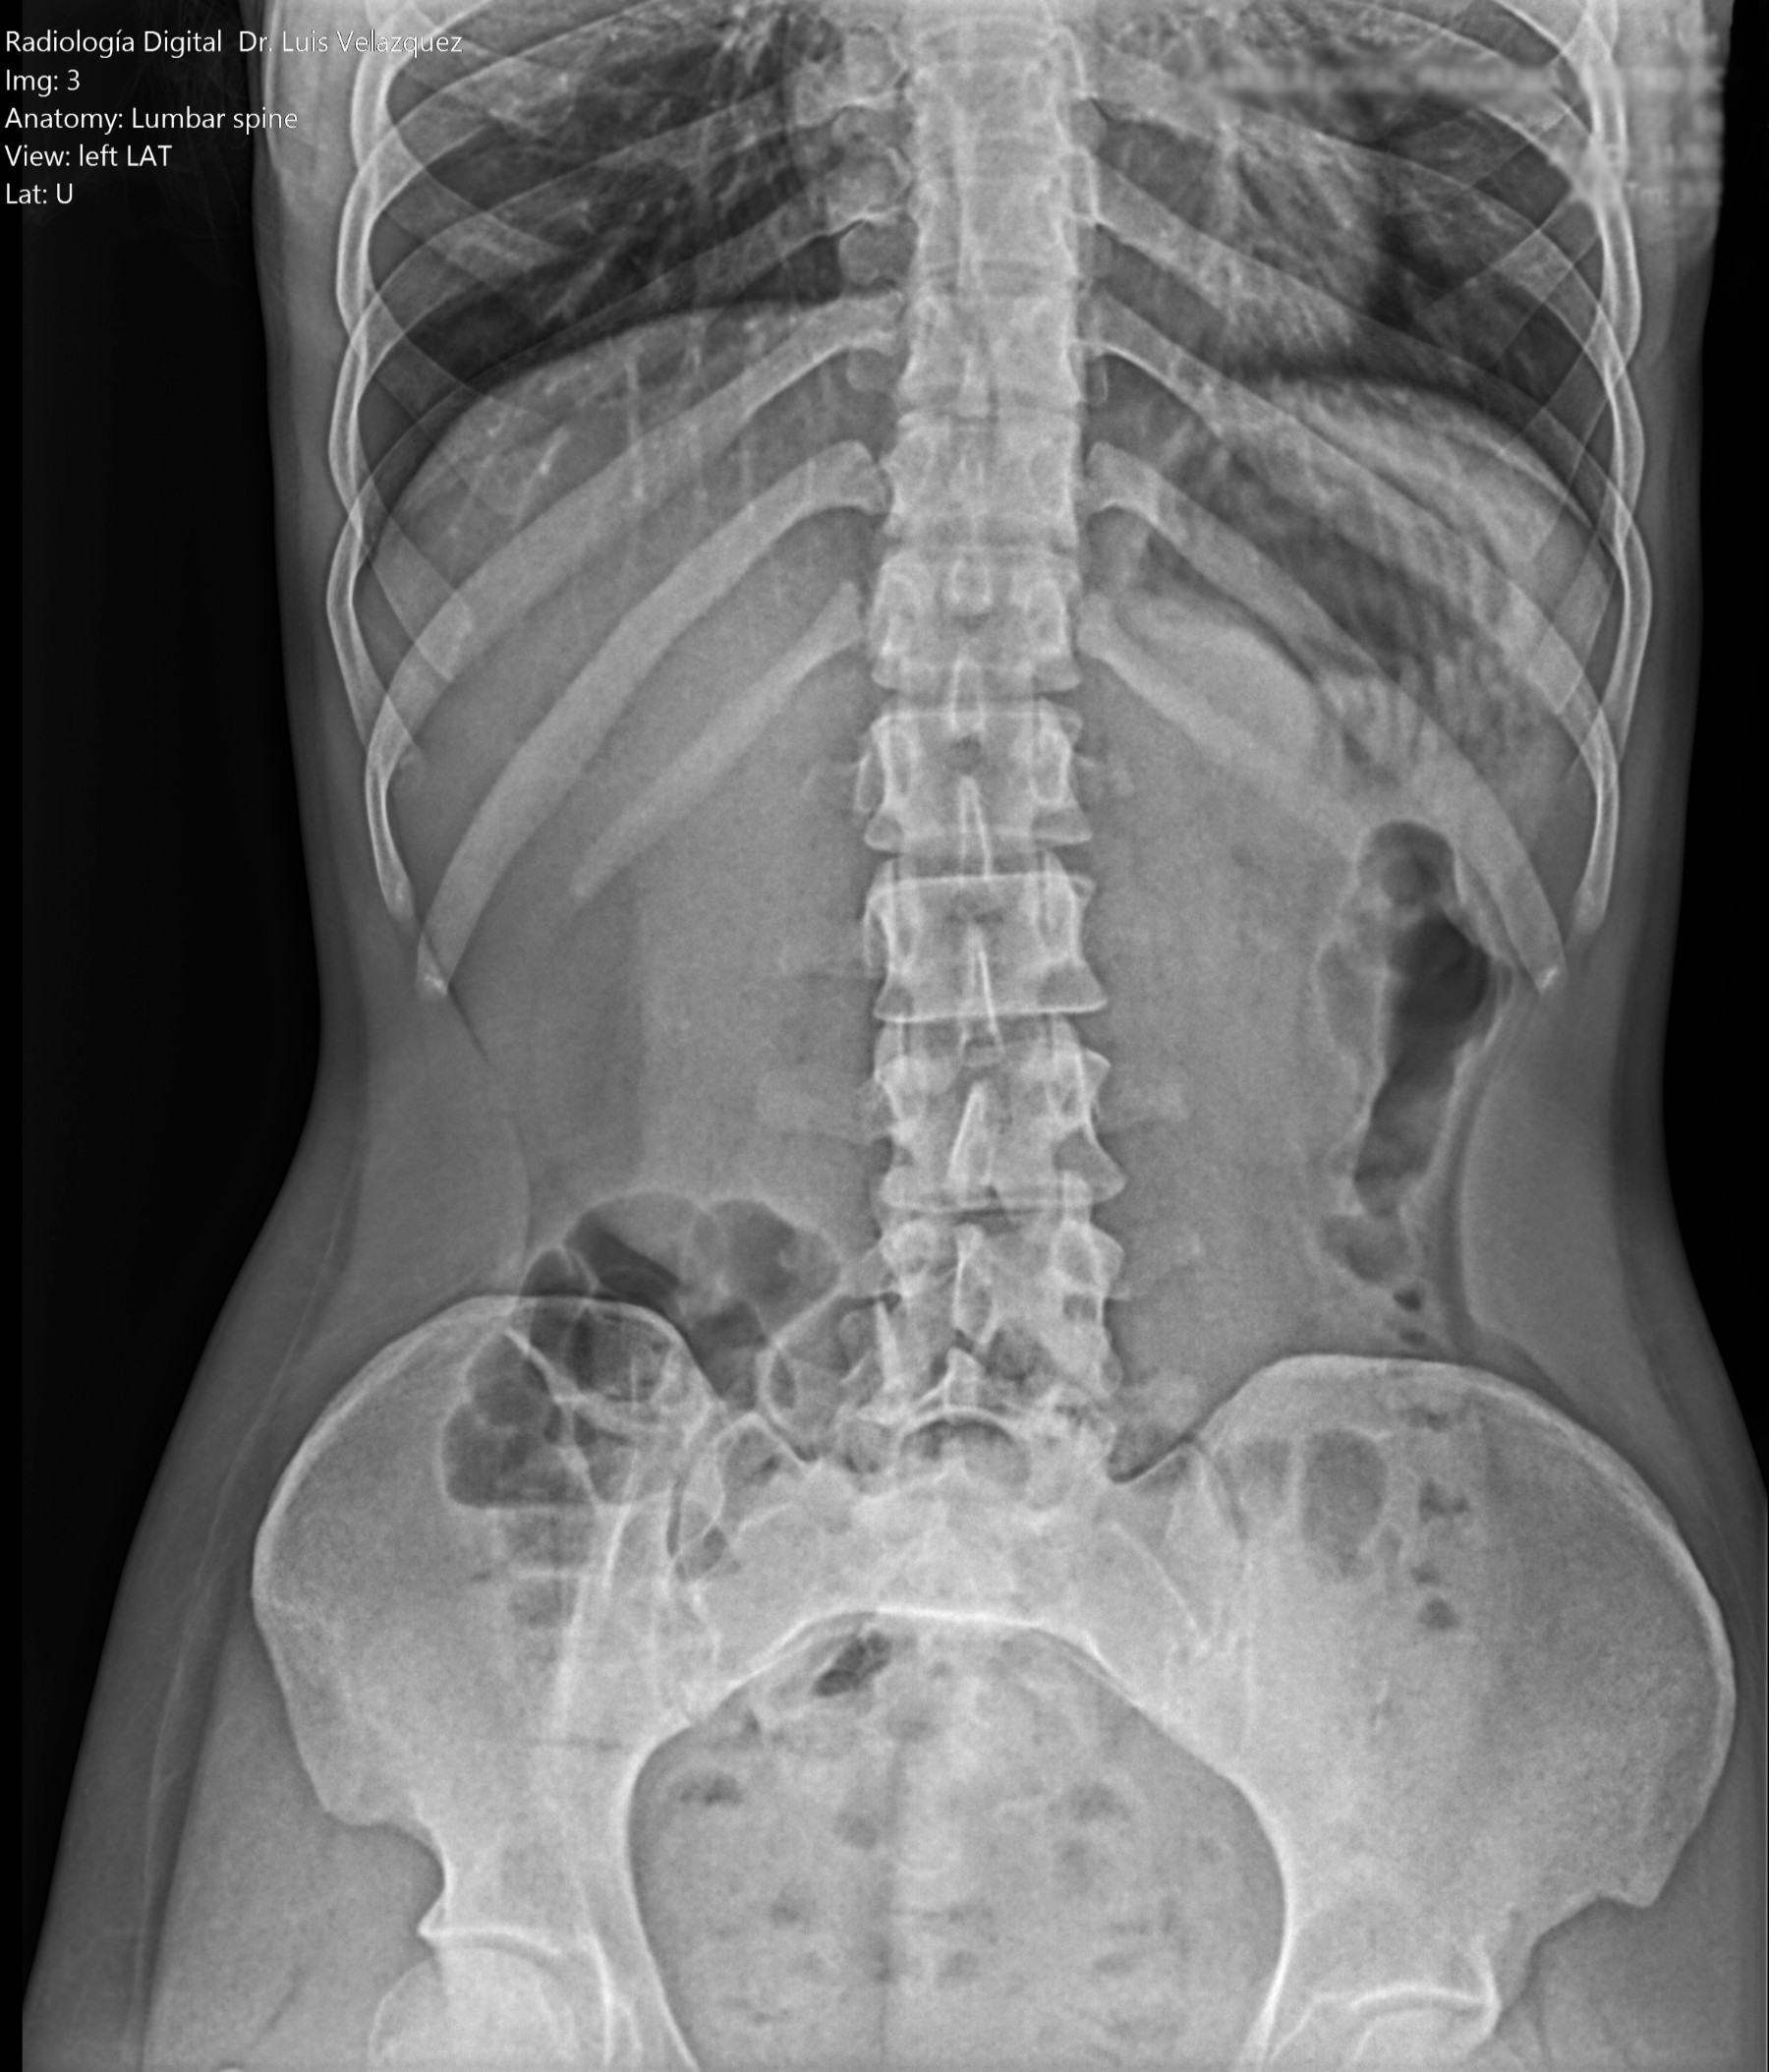

Radiología Digital como Herramienta Complementaria en el Dictamen de Bienes Muebles

Desde el descubrimiento de los rayos “X” y las placas radiográficas por Wilhelm Conrad Roentgen y su posterior difusión a través de la Asociación Físico médica de Wurzburg el 28 de diciembre de 1895, que fue la primera asociación que habló de los nuevos rayos que podían penetrar el cuerpo y fotografiar los huesos, ha habido muchos cambios tanto en la forma de obtener, procesar e incluso en la forma de visualizar, manejar y almacenar las placas radiográficas.